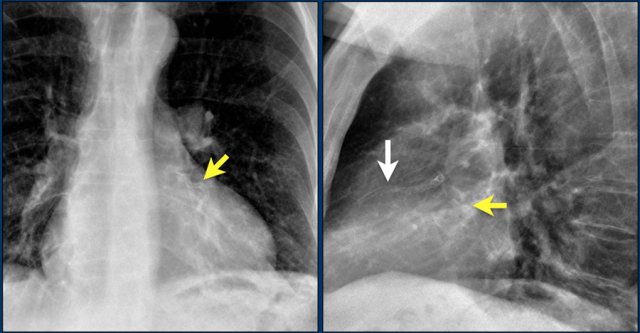

Here a patient with a normally placed ICD on the left image.

Months later there was malfunction due to ICD box and lead rotation (yellow arrow) and retraction (white arrow).

Here another patient with the Twiddler's syndrome.

Notice curling of the lead near the pacemaker and at the tip in the right ventricle (arrows).